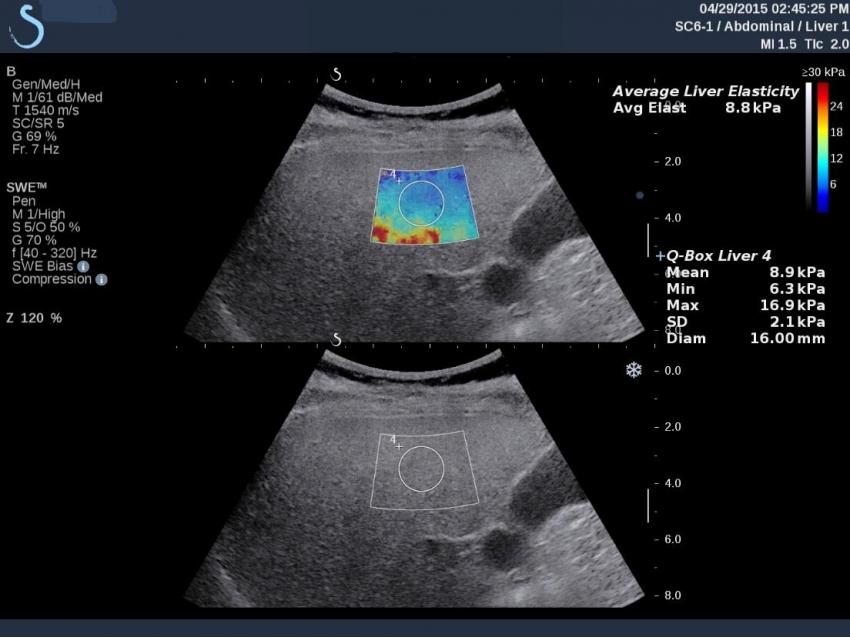

Shear wave elastography (ARFI) is a modern method which is increasingly used in the world healthcare industry to examine the liver using ultrasound machines. It has several advantages when compared to other non-invasive diagnostic methods. This mode is already widely used by many manufacturers, such as GE Healthcare, Philips, Siemens, and SuperSonic, but unfortunately, this method is not yet standardized, does not have an ARFI measurement quality scale, and each manufacturer uses its own interpretation. Shear wave elastography (ARFI) is 90% accurate due to the wavelength index averaging when tissue elasticity is assessed.

Using transient elastography (TE) technique with the FibroTouch device, the obtained data on the liver condition corresponds to stage F1 to F4 disease in the kPa and correlates with the histological fibrosis stage according to the METAVIR scale, as well as takes the IQR measurement quality and reliability scale into account.